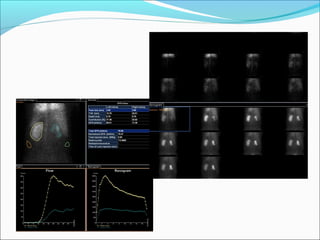

Diuretic Renal Scan

Principle

Tracer pooling in dilated renal pelvis

Lasix induces increased urine flow

If obstructed >>> will not wash out

If dilated, non-obstructed >>> will wash out

Can quantitate rate of washout (T1/2)

Washout (diuretic response)

T1/2

Time required for 50% tracer to leave the dilated unit i.e.

time required for activity to fall to 50% of peak.

Normal < 10 min

Obstructed > 20 min

Indeterminate 10 - 20 min

Diuretic Renal Scan Interpretation

Interpret whole study, not T1/2 alone

Visual (dynamic images)

Washout curve shape

 T1/2